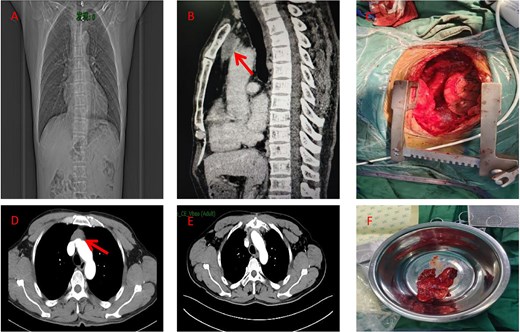

A male in his 60s presented to our hospital with chest pain for a week. The patient had undergone coronary stenting in 2021. A computed tomography (CT) scan of the chest showed a round isointense mass in the anterior mediastinum measuring ~37 × 15 mm (Fig. 1A and B). Contrast-enhanced CT of the tumor showed mild homogeneous enhancement with punctate calcification (Fig. 1D). During surgery, the tumor was found to invade the left brachiocephalic vein and the lateral wall of the superior vena cava with evidence of nerve bundle involvement. Therefore, the patient underwent median sternotomy with total resection of the tumor (Fig. 1C), including the involved brachiocephalic vein, pericardium, and partially resected superior vena cava, and removal of peritumoral lymph nodes. Gross examination of the resection specimen revealed a tumor with a maximum diameter of 7 cm (Fig. 1F). The section was grayish-white and firm, and the internal mass measured 5.2 × 4 × 2 cm. Histopathologic examination under the microscope showed that the cancer cells were arranged in a glandular and wedge-shaped pattern, floating in pools of mucin. The cells exhibited marked atypia and showed infiltrative growth (Fig. 2A). Pathologic analysis of the margins of the specimen and the stump of the brachial vein showed no evidence of cancer cell involvement. Examination of six peritumoral lymph nodes revealed no metastatic cancer. Immunohistochemical staining results were as follows: CK (+), CK20 (−), CK7 (−), caudal-type homeobox transcription factor 2 (CDX-2) -2(+), villin (+), TTF-1 (−), P63 (−), S100 (−), CD5 (−), and Ki-67 of ~50% (magnification ×100) (Fig. 2). Post-operative pathological diagnosis confirmed mucinous adenocarcinoma. Pathological the patient received radiotherapy 1 month after surgery. Three months post-operatively, a follow-up chest CT performed in our hospital showed poorly structured layers with patchy areas of mild hypodensity in the operated area and no enhancement on contrast-enhanced scanning (Fig. 1E). The patient remains alive 6 months after surgery.

(A) Preoperative chest X-ray (coronal view). (B) Preoperative CT scan (sagittal view) showing the anterior mediastinal mass (arrow). (C) Intraoperative view of the resected specimen. (D) Preoperative CT scan (axial view) showing the anterior mediastinal mass (arrow). (E) Post-operative imaging at 3 months following surgery and radiotherapy (RT). (F) Photograph of the surgical specimen.